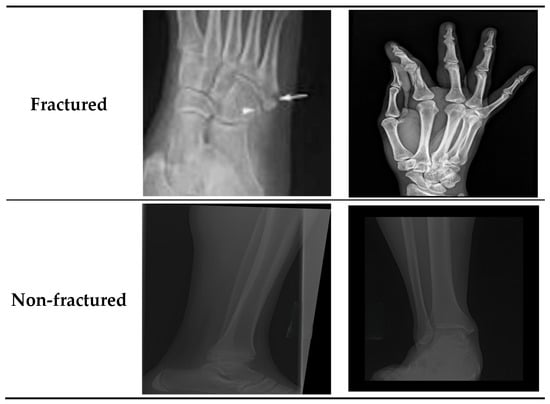

The BFMRX dataset used in our study was sourced directly from Kaggle [29] and was utilized as provided by the dataset authors, without any alterations to the original training, validation, or test splits. According to the dataset description on Kaggle, the splits were prepared by the dataset creators, ensuring that images from the same patient do not appear in multiple subsets. The BFMRX dataset from Kaggle [29] contains X-ray images of both fractured and non-fractured regions of the body, encompassing areas such as the lower limb, upper limb, lumbar spine, hips, and knees. The sizes of the X-ray images differed, requiring preprocessing steps to normalize the data before it could be fed into the models. This dataset includes a total of 10,580 radiographic images (X-ray data). The BFMRX dataset is organized into an 87% training set (9246), a 5% testing set (506), and an 8% validation set (828). Table 1 and Figure 3 and Figure 4 display the allocation of images categorized into fractured and non-fractured groups. Figure 5 shows samples from the BFMRX dataset.

• Contrast Enhancement: Image contrast was enhanced to reduce sensitivity to lighting variations in radiographic scans and to improve the visibility of subtle fracture patterns. Figure 7 shows the images before and after contrast enhancement.